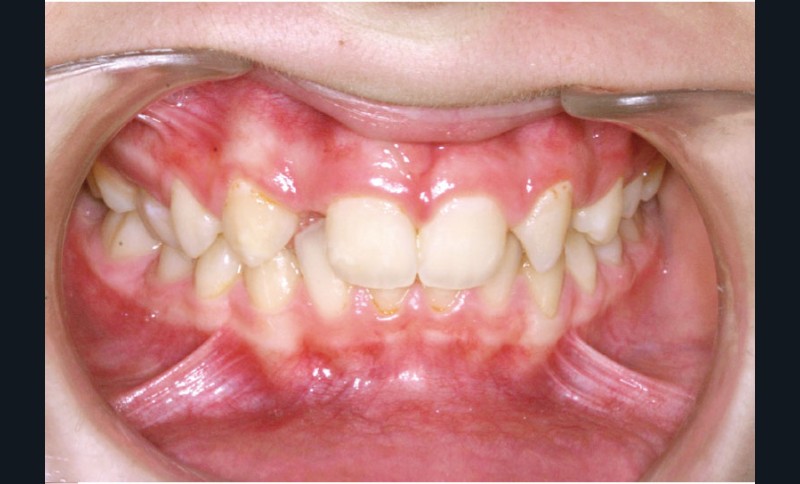

Ludivine T. âgée de 12 ans et demi présente une agénésie des deux incisives latérales maxillaires dans un contexte occlusal de classe II division 2 (fig. 1 à 3).

Les vues endo-buccales (fig. 2) montrent la classe II division 2 occlusale associée à une forte supraclusion incisive et l’évolution spontanée de 13 et 23 pratiquement en place de 12 et 22. Il persiste cependant un diastème disgracieux entre 13 et 11.